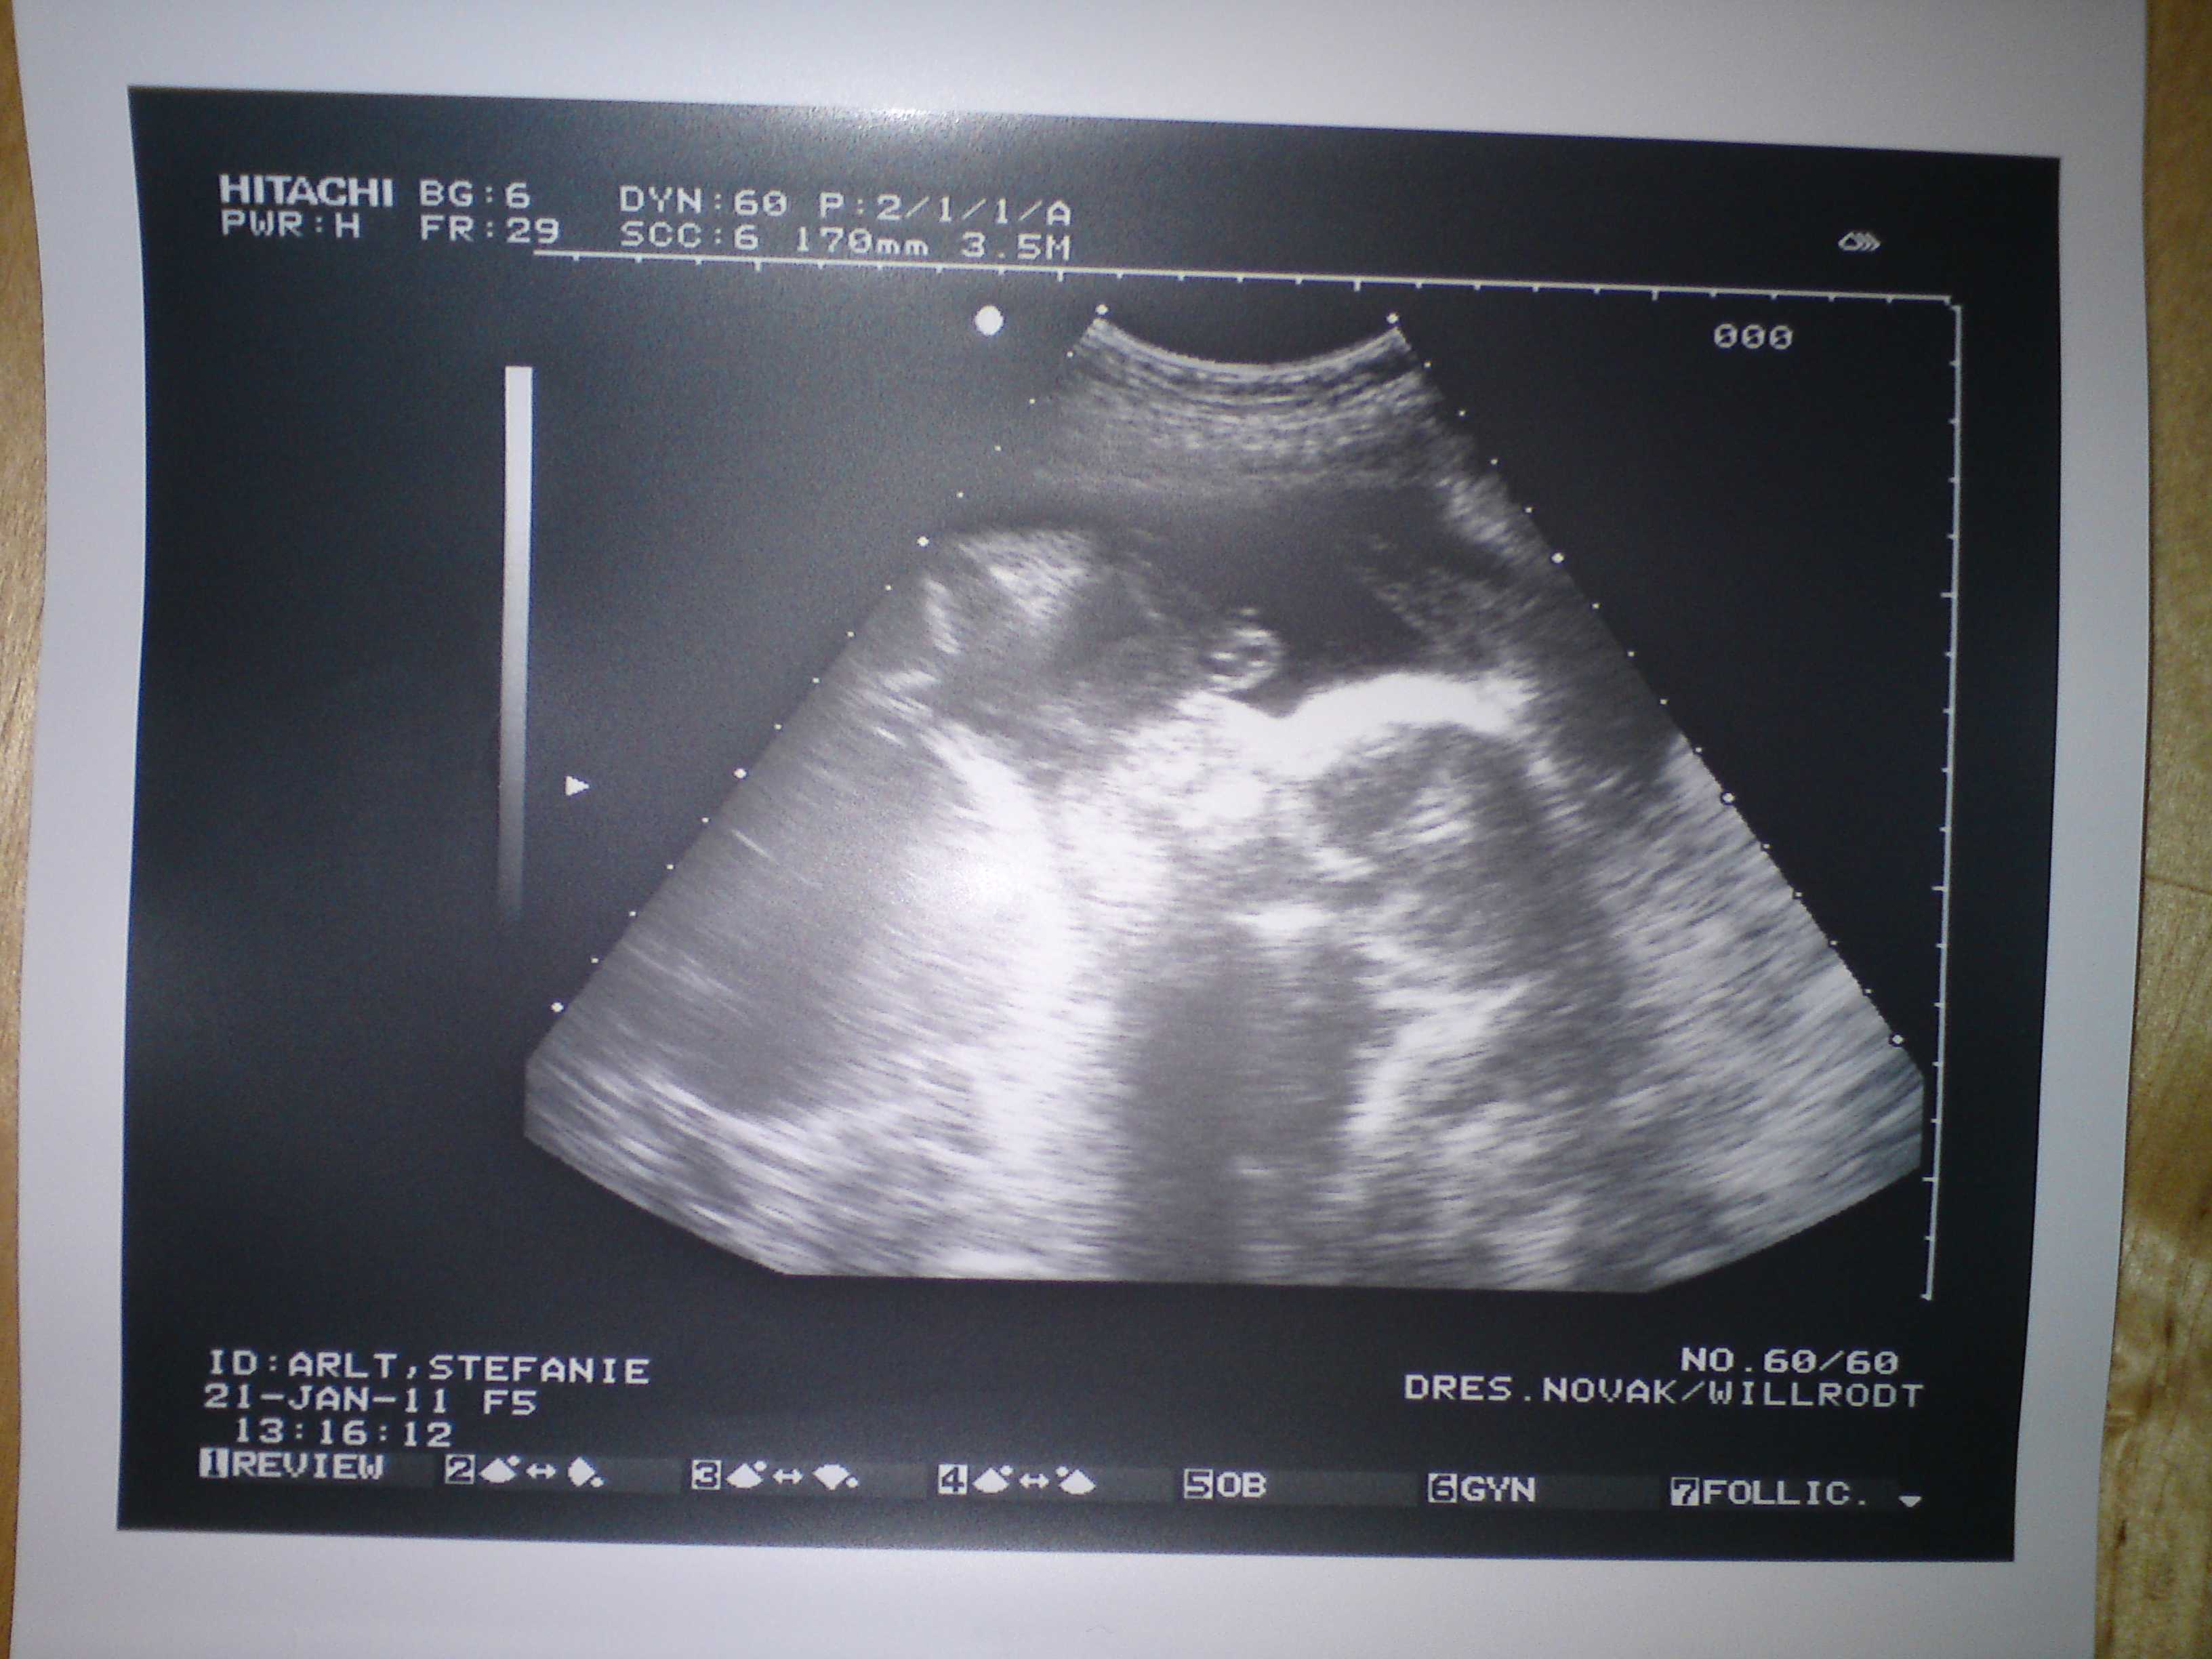

@all: wir waren heute zum Erst-Trimester-Screening und erstmals war auch mein Mann mit. Er hat sich ja bisher erfolgreich „gedrückt“, weil er Angst hatte, dass er mitkommt und dann ist wieder das Baby tot. Er hat das ja nun auch schon 2 x miterlebt.

Das Baby war zum Glück nicht tot und es war wie immer ein tolles Erlebnis, so ein ausführlicher Ultraschall.

Auch ist alles bestens, die Nackentransparenz liegt bei 1,04 mm, also top.

Babylein misst 78,5 mm (SSL), mit Beinen ist er/sie also schon ca 12 cm groß (laut FA).

Sie hat heute auch eher zum Jungen tendiert, aber so richtig günstig lag das Baby heute nicht. Naja es bleibt echt spannend.

Nach dem Ultraschall sank mein Hintergrundrisiko für Trisomie 21 von 1.486 auf 1:2684, das Hintergrundrisiko für Trisomie 13/18 sank von 1:974 auf 1:5945, ich habe laut der FA ein Risiko wie eine 16-Jährige. Klingt alles gut.

Wir sind sehr happy und mein Mann war echt begeistert, was man da schon so alles sieht. Ich glaube, das war gut, dass er sein Kind auch mal in Aktion gesehen hat (Baby hat nämlich ausgesprochen wild geturnt

), so bekommt er eher eine Bindung und Vorstellung.

Anbei noch zwei Bildchen.